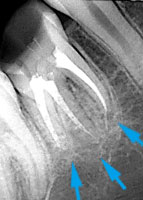

歯根の先に大きな膿がありました。

2年後、骨が再生しています。